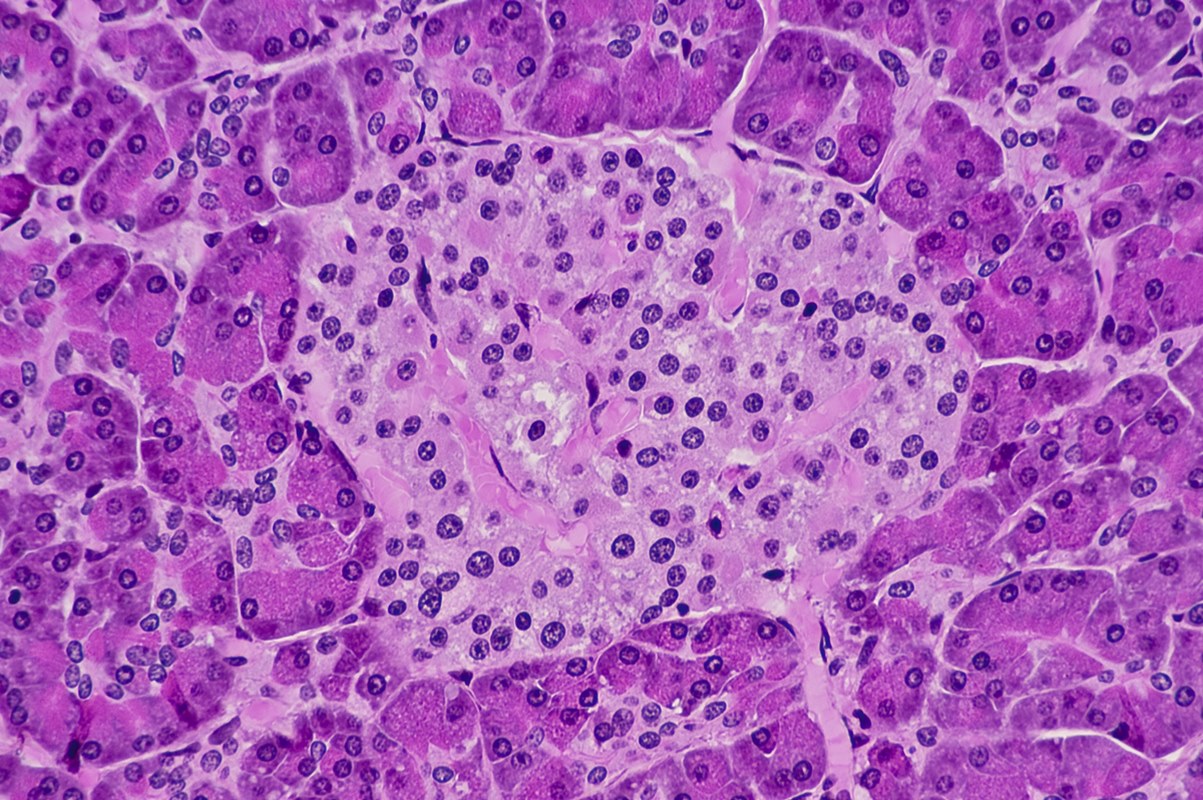

Pesquisadores da Universidade Metropolitana de Osaka, no Japão, identificaram que o gene REDD2, ativado por estresse metabólico, prejudica as células β (beta) do pâncreas responsáveis pelo controle de açúcar no sangue e pela produção de insulina.

Em experimentos com culturas celulares e camundongos, foi possível observar que os altos níveis de glicose, ácidos graxos e substância para induzir diabetes (STZ) estimularam o REDD2, levando à morte celular e inibição da via mTORC1 – complexo proteico responsável pela regulação do crescimento das células.

Camundongos sem REDD2, mesmo em dieta rica em gordura ou exposição a agentes que induzem a diabetes, mantiveram mais células saudáveis, produzindo mais insulina e exibindo um melhor controle da glicose.

A análise de ilhotas pancreáticas humanas reforçou esses achados: níveis elevados de REDD2 estão associados à redução na massa das células β e diminuição da secreção de insulina.